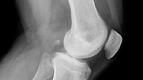

Har man knogleskørhed, har man nedsat knoglemasse, og ens knogler brækker derfor lettere end andres. Ubehandlet knogleskørhed øger markant risikoen for brud på fx rygrad, underarm, håndled, lårben og hofte.

Næsten hver 3. kvinde og hver 6-8. Mand, der i dag er fyldt 50 år, vil på et tidspunkt blive ramt af mindst ét knoglebrud som følge af knogleskørhed. Mange får flere brud, der – afhængigt af type og antal – kan få fatale følger for den enkeltes livskvalitet og muligheder for at klare sig uden hjælp.

Hvert år behandles mindst 35.000 brud pga. knogleskørhed i Danmark.

Hvert andet brud, der rammer et mennesker over 50 år, skyldes knogleskørhed.